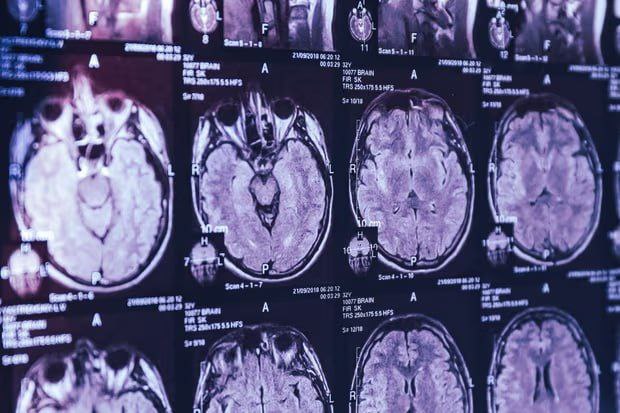

Один из ведущих ученых Канады заявил о загадочной болезни головного мозга, от которой страдают около 350 человек. По его словам, правительство страны запретило исследовать это заболевание, сообщает Guardian со ссылкой на электронные письма.

В начале июня издание также сообщило, что ученому Майклу Култхарту запретили исследовать загадочное заболевание головного мозга в провинции Нью-Брансуик, которым болеют более 200 человек.

Култхарт указал, что воздействие окружающей среды или их комбинация может запускать или ускорять различные нейродегенеративные синдромы у людей, предрасположенных к заболеваниям, связанным с неправильным сворачиванием белков, таким как болезнь Альцгеймера и болезнь Паркинсона. Он утверждает, что сложность этой проблемы позволила политикам закрыть для ученых возможность исследования.

По данным газеты, в 2021 году здравоохранение провинции Нью-Брансуик предупредило, что более 40 жителей страдают от неизвестного неврологического синдрома с разнообразными симптомами, такими как слюнотечение и ощущение ползания насекомых по коже. Однако год спустя независимый комитет пришел к выводу, что группе пациентов, вероятно, был поставлен неверный диагноз, и что они страдают от известных заболеваний, таких как рак и деменция. Вследствие этого было решено прекратить все исследования.